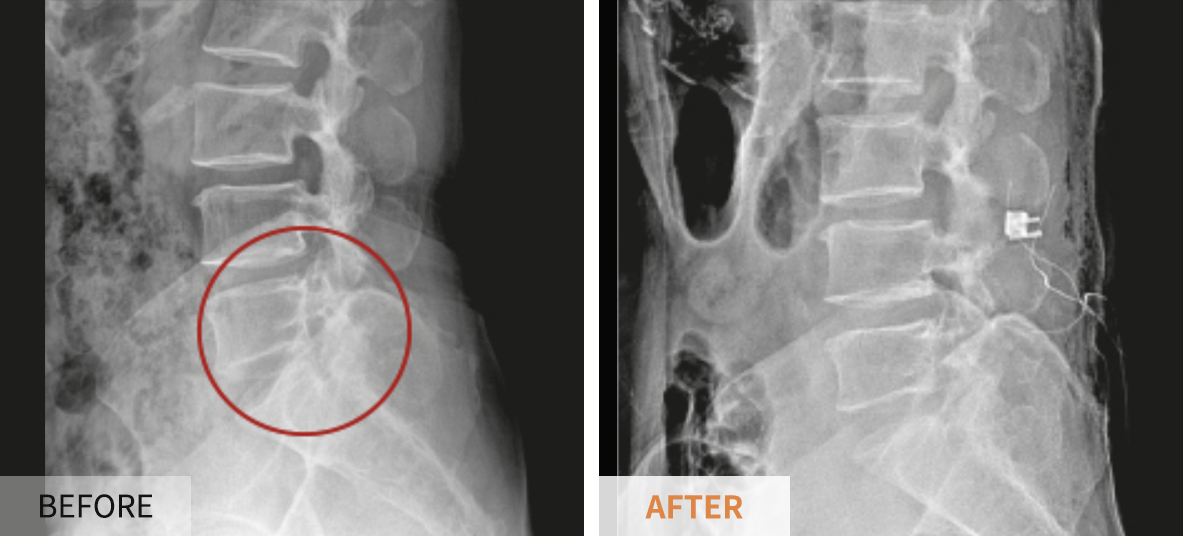

- 척추관 확장술: 좁아진 신경통로를 넓히는 수술로, 신경을 압박하는 구조를 제거하게 됩니다.

- 척추 고정술: 척추 불안정을 동반할 경우, 척추를 고정하여 안정성을 높입니다.

수술은 효과적일 수 있지만, 항상 위험을 동반하기 때문에 충분한 상담과 평가가 필요합니다. 수술 후에는 재활치료가 필요하며, 이를 통해 정상적인 운동 범위를 회복할 수 있도록 합니다.